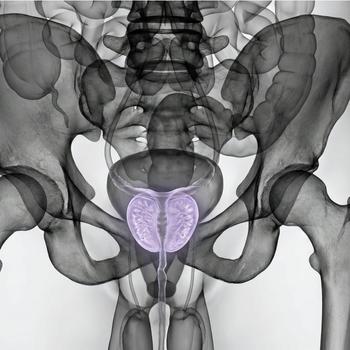

MRI Pelvic – for gynecological problems, cysts or suspected endometriosis

If you have pain in the lower abdomen, irregular bleeding, fertility problems or suspect that something is not right in the lower abdomen, an MRI examination of the pelvis can be the next step to get the right diagnosis. MRI pelvic, also called MRI gynecology, is a painless and radiation-free examination that provides very detailed images of both the uterus, ovaries and fallopian tubes.

The examination is used when other methods such as ultrasound or gynecological examination have not been able to explain your symptoms. With the help of MRI, conditions such as endometriosis, fibroids, cysts, tumors, malformations or effects on nearby organs such as the bladder or intestines can be detected. It is also an important method before fertility treatment or in preparation for surgery.

Whether you are seeking answers to long-term symptoms or following up on previous findings, pelvic MRI gives you and your doctor a clear picture that can form the basis for the right treatment and continued care.